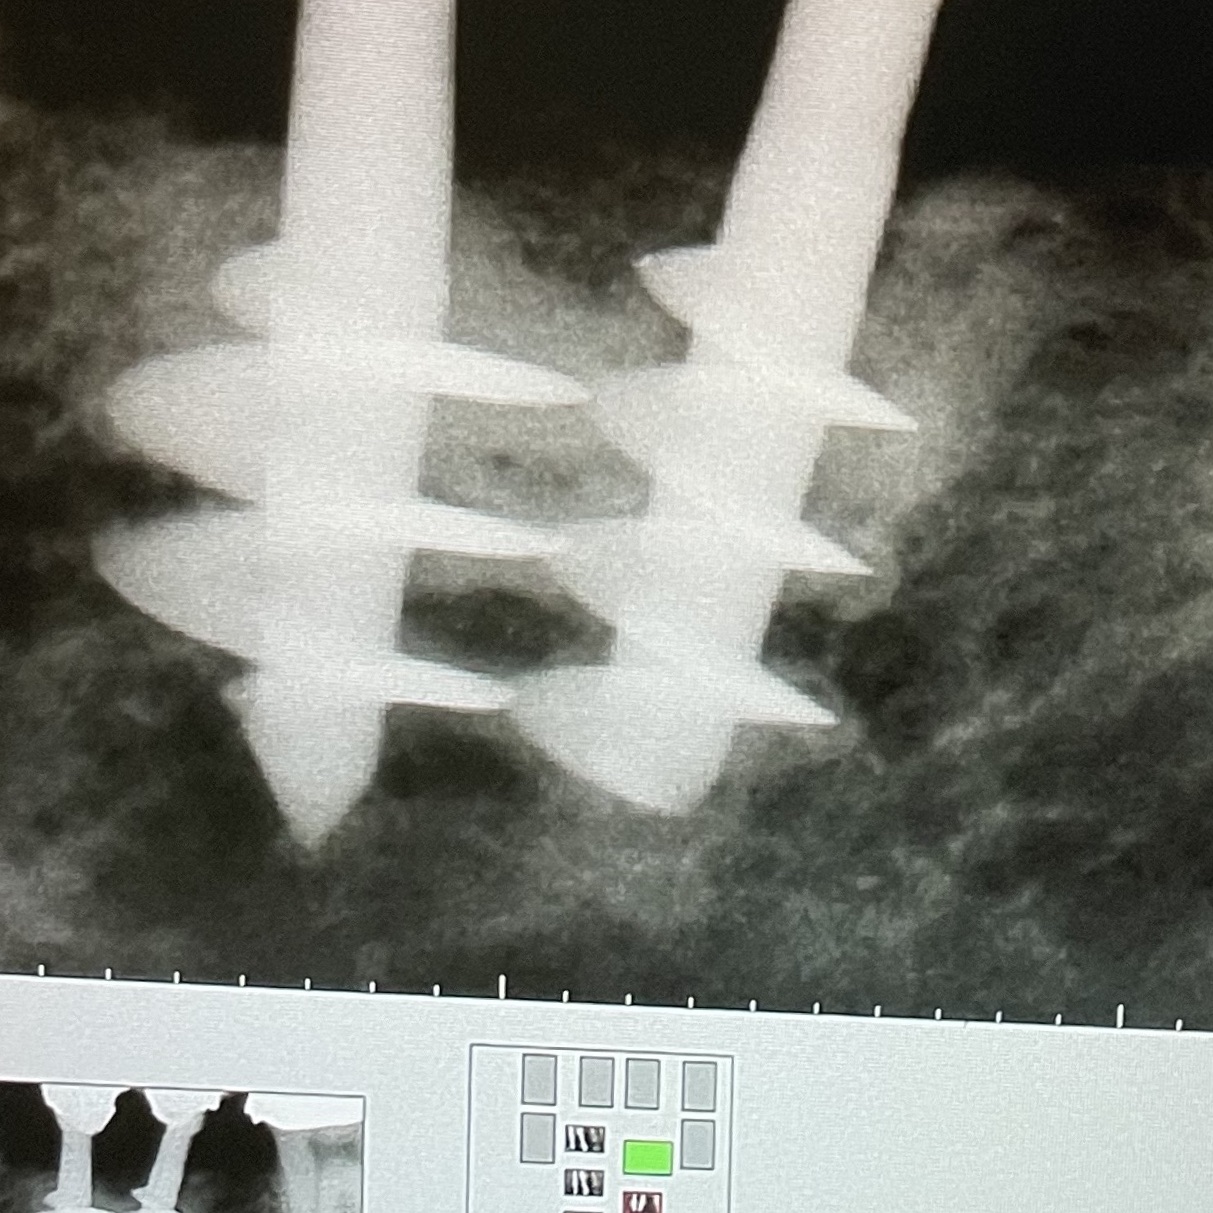

8 - POSITIONING TIMING: PERFORATION OF THE CORTICALS

News n. 8 29/01/2021